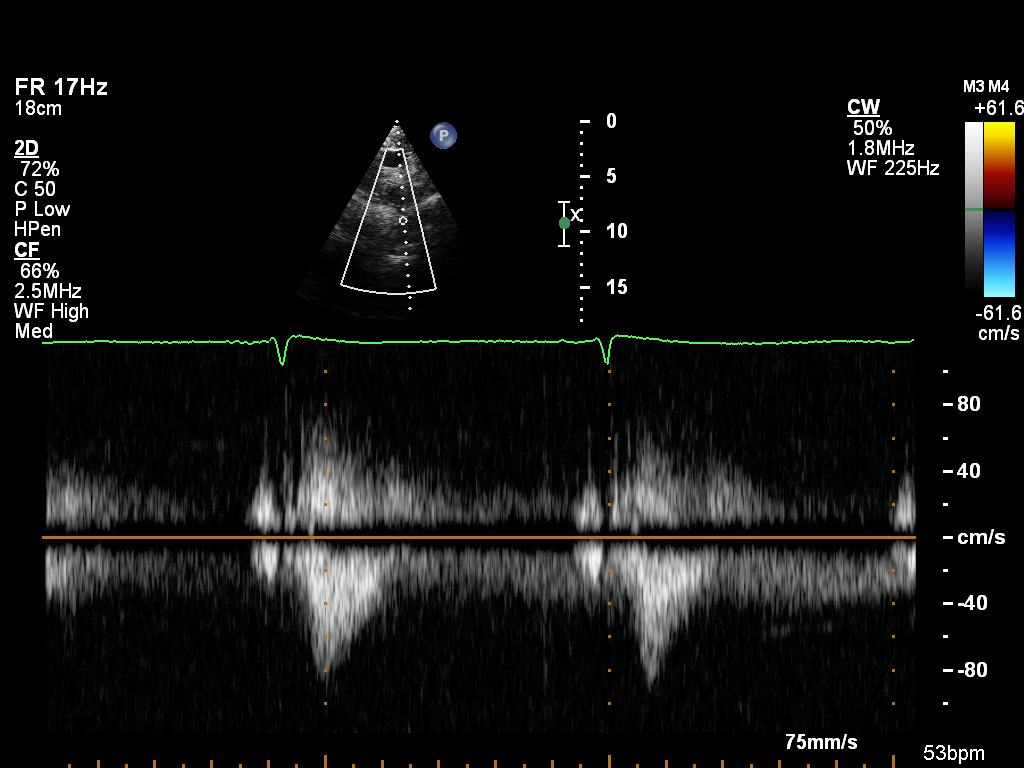

doppler-tv doppler-tv Spectral Doppler of the tricuspid valve

License & Ethics